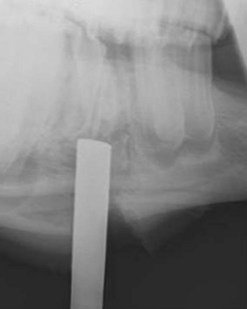

After the apex of a diseased cheek tooth has been exposed using techniques described above, the tooth is repulsed into the oral cavity by striking a dental punch applied to the apex of the tooth and aligned in the direction of the tooth’s path of eruption. Confirming the position of the punch radiographically ensures that the punch is properly aligned (Fig. 20.48). Failure to align the punch correctly may result in damage to a neighboring tooth, the palatine bone, if the tooth is maxillary, or to the internal or external lamina of the mandible, if the tooth is mandibular. When the punch is aligned obliquely to the long axis of the tooth, more force is required to repulse the tooth because the periodontium is not disrupted as efficiently as when the punch is properly aligned. The extra force required is more likely to result in bony or dental sequestra. Because the reserve crowns of the cheek teeth curve axially in a coronal to apical direction, and because the mandibular and infraorbital nerves lie slightly medial to the center of the teeth, applying the punch slightly lateral to the central axis of the tooth reduces the risk of damaging these nerves.

image

Fig. 20.48 When repulsing a tooth into the oral cavity, the punch should be aligned in the direction of the tooth’s path of eruption. Confirming the position of the punch radiographically ensures that the punch is properly aligned. The punch seen in this radiographic projection is in close alignment with the longitudinal axis of the tooth.